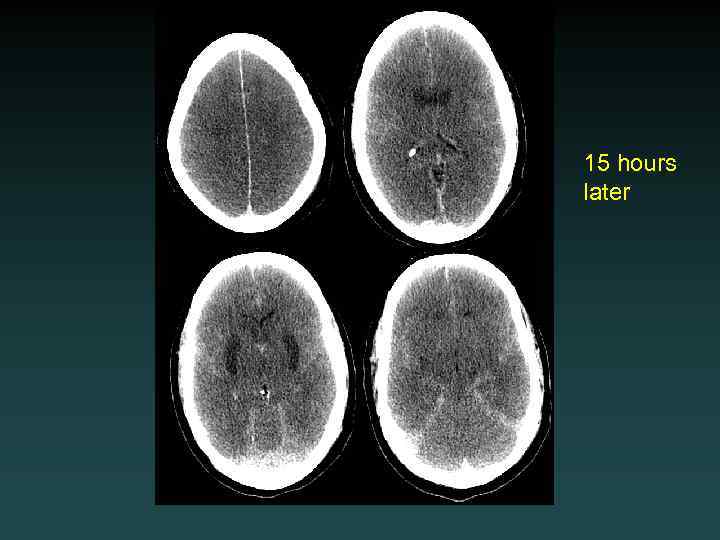

Watershed Infarction

15 hours later